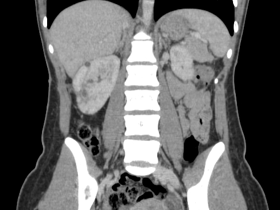

Imagens associadas à LAM e à esclerose tuberosa

Angiomiolipoma renal bilateral

Angiomiolipomas renais